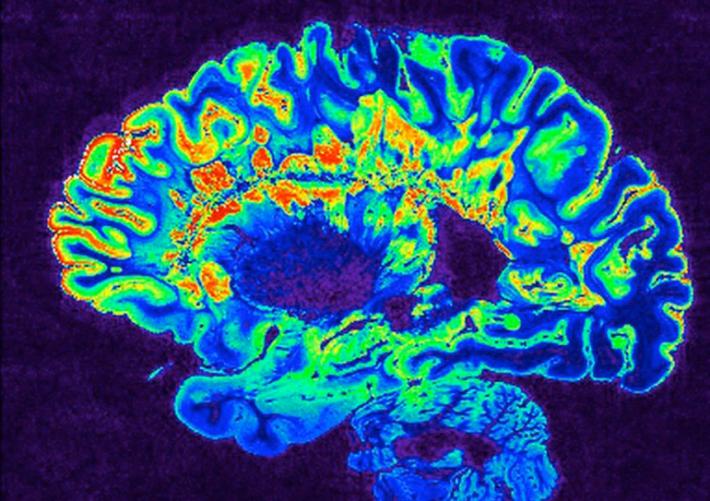

cervello sclerosi multipla